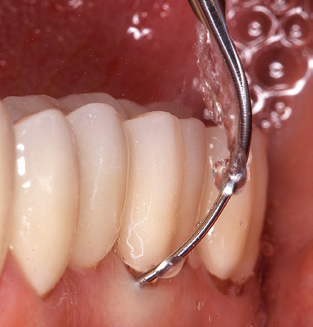

The current working concept for SPT

Fig. 4: Flexible probes with millimetre markings are recommended for the probing of dental implants (e.g. Colorvue Kit PCV11KIT6, Hu­Friedy). – Fig. 5a and b: A straight working tip (1P, W&H Dentalwerk Bürmoos GmbH) is a suitable instrument for use on all natural teeth. – Fig. 6: Curved working tips (3Pr/3Pl, W&H Dentalwerk Bürmoos GmbH) lend themselves to the processing of difficult-to-reach areas of the tooth and root surfaces (e.g. furcations). – Fig. 7: The tapered, hexagonal implant cleaning tip (1I, W&H Dentalwerk Bürmoos GmbH) permits atraumatic and efficient cleaning of the crown and abutment surfaces. – Fig. 8: Titanium and carbon curettes are suitable instruments for the manual cleaning of the implant surfaces.